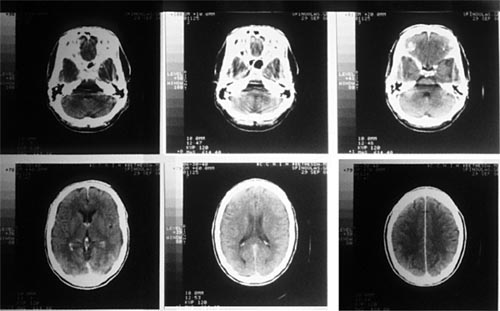

【廣東高尚醫(yī)學(xué)影像】CT檢查全過(guò)程詳解

CT掃描儀用X射線作為掃描光線,跟傳統(tǒng)的X光掃描不同的是CT掃描儀不只是拍攝一張圖片,而是會(huì)拍攝不同截面的多張圖片,之通過(guò)系統(tǒng)將拍攝的圖片合成完整的三維圖像,恢復(fù)被掃描的內(nèi)部結(jié)構(gòu)。

傳統(tǒng)X射線最大的局限在于,傳統(tǒng)的X射線只能提供二維的圖片,因此無(wú)法提供器官或身體其他部位內(nèi)部結(jié)構(gòu)的具體信息,真實(shí)反映出檢測(cè)部位的三維結(jié)構(gòu)。此外,人體許多不同的組織對(duì)X射線有相近的吸收能力,導(dǎo)致無(wú)法通過(guò)X射線區(qū)分這些不同的組織。并且在傳統(tǒng)的X射線檢測(cè)中,會(huì)有大量的射線被散射掉,導(dǎo)致圖像很不完整。而CT掃描不僅可以提供被檢測(cè)部位內(nèi)部結(jié)構(gòu)的三維圖像,還可以區(qū)分不同的組織,并將X射線集中在特定的檢測(cè)區(qū)域,從而得到更清晰的圖像。